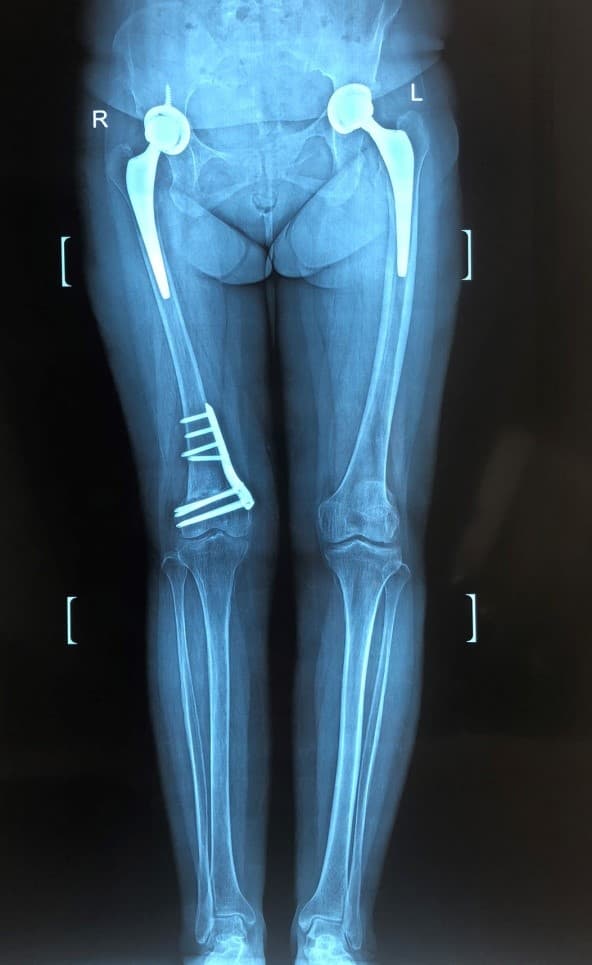

Түнхний төрөлхийн дутуу хөгжил, мултралын улмаас хоёр түнхний үеийг солих мэс засал хийгдсэн эмчлүүлэгчид хийгдсэн саруй хөл засах мэс заслын өмнөх болон дараах рентген зураг

Саруй хөл нь ихэвчлэн өвдөгний гадна хэсэгт ирэх ачааллыг нэмэгдүүлж өвдөлт зовиур үүсгэдэг тул засагдсанаар өвдөгний остеоартритын явц удааширч, өвдөлт зовиур арилж, хөл тэгширч, хөлийн урт богины зөрүү багасдаг.